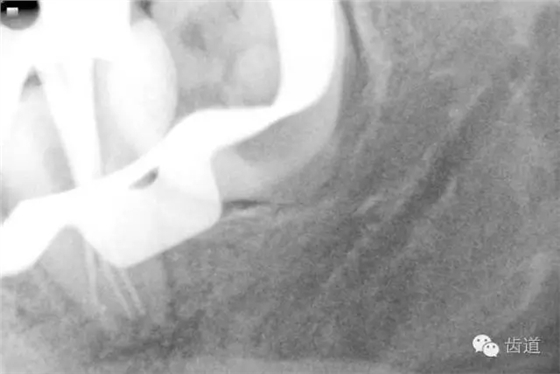

4. 術(shù)后根充X線片

二診(2015.02.02): 主訴:復(fù)診,癥狀消失,無不適。 檢查:37暫封無缺損,探痛-,叩痛-,松動(dòng)-,牙齦無紅腫。 治療過程:37橡皮障放置,顯微鏡下,去盡暫封,5ml 2%氯己定溶液沖洗,超聲蕩洗,清理,干燥,Iroot SP糊劑+牙膠熱壓充填根管,拍攝x線片顯示根充密實(shí),恰填。回切牙膠至保留根尖5mm,SDR流動(dòng)樹脂充填根中上三分之二及髓腔,光固化20s,玻璃離子暫封。